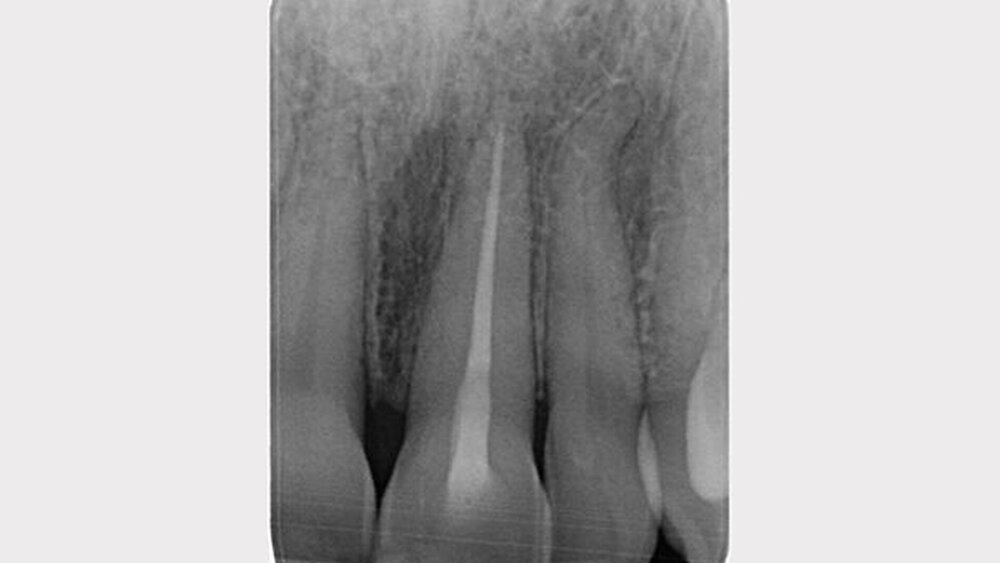

Zum Ausschluss von Kiefer- beziehungsweise Gelenkfrakturen wurde ein OPG erstellt. Sichtbar waren die Dislokation von 21 und die Zahnkronenfraktur an Zahn 11. Das restliche OPG war o.p.B..

Zur Detaildiagnostik war ein Zahnfilm von 11 und 21 indiziert. An Zahn 11 war neben der Kronenfraktur ein geringfügig erweiterter Parodontalspalt sichtbar. An Zahn 21 war eine Infraposition durch Dislokation in nicht axialer und in apikaler Richtung sichtbar. Weitere bildgebende Verfahren waren nicht nötig.

Vor der Fortsetzung der Wurzelkanalbehandlung an 21 war ein Zahnfilm indiziert, da der inzisale Referenzpunkt nach dem Aufbau verändert war. Temporärer Verschluss und Ledermix wurden entfernt. Das Wurzelkanalsystem erschien o.p.B.. Die elektronisch bestimmte Arbeitslänge wurde mittels Zielaufnahme bestätigt. Der fertig aufbereitete Wurzelkanal entsprach dieser in der Länge, umschloss den ursprünglichen Kanal und erhielt die apikale Konstriktion. In den getrockneten Kanal wurde Calciumhydroxid eingebracht und der Zahn temporär verschlossen.

Ein Monat posttraumal erfolgte nach anhaltender Beschwerdefreiheit die Wurzelfüllung durch vertikale Kondensation. 12-22 waren fest, perkussionsnegativ und außer 21 vital. Das Weichgewebe war verheilt und die Gingivarezessionen waren stabil. Entzündungszeichen, ankylotischer Klopfschall, pathologische Sondierungswerte, Frakturen und Zahnkronenverfärbungen konnten ausgeschlossen werden. Die Palpation war o.p.B.

Die Guttapercha wurde unter der Schmelz-Zement-Grenze abgetrennt, um späteren Zahnverfärbungen vorzubeugen. Die Wurzelfüllung war röntgenologisch o.p.B. Die Deckfüllung erfolgte zur Prävention einer Kontamination oder Fraktur mittes definitiver Kompositfüllung.

Nach 24 Monaten wurde die Wurzelfüllung an 21 mittels Zahnfilm kontrolliert. Der Heilungsverlauf war o.p.B.. Für ein gutes Ergebnis der Wurzelkanalbehandlung sprachen der unauffällige Parodontalspalt, keine Fistel, kein Funktionsverlust, keine Schwellung und die anhaltende Schmerzfreiheit.